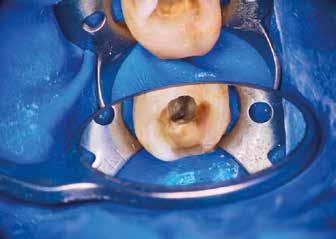

Helyi érzéstelenítést követően kofferdám került felhelyezésre, majd az izolálást folyékony kofferdám felvitelével (RUBBER-DAM liquid, CERKAMED) erősítettük meg (2. ábra). Ezt követően az ideiglenes tömést eltávolítottuk és a pulpakamrát desztillált víz, valamint ultrahangos hegyek segítségével aktivált 5,25%-os NaOCl oldattal megtisztítottuk (3. ábra). Az első mesio-bukkális (MB1), a diszto bukkális (DB) és a palatinális (P) gyökércsatorna átjárható volt, ezért először egy C-PILOT tű (VDW) és egy elektromos apexlokátor (E-PEX, Eighteeth) segítségével ezekben a csatornákban a munkahossz meghatározásra került. Ezután a gyökércsatornákat nagyjából az eredeti munkahossz kétharmadáig

reciprok mozgást végző gépi gyökérkezelő tűkkel feltágítottam (#25/.07 Perfect Shape; Shenzhen Perfect Medical Instruments). Ezt követően az MB2 gyökércsatorna bemeneti nyílását fedő dentint egy gyémánt borítású ultrahangos fej segítségével eltávolítottam (ED3D, Woodpecker). A terület vizsgálatát követően észleltem, hogy az MB1 és MB2 csatornákat egy vékony résszerű nyílás (isthmus) köti össze. Az MB2 csatornának csak a koronális harmadát volt lehetséges kézi eszközök segítségével megmunkálni (4. ábra). Az MB csatornák között lévő rést 2 mm mélységben az előzőleg használt gyémánt borítású ultrahangos fejjel eltávolítottam (5. ábra)

Az átöblítés során a roots magazin egy korábbi számában (2/2022) bemutatott protokollt alkalmaztam (Less-Prep Endo enhanced irrigation protocol). Az átöblítőszer aktiválása SkyPulse lézer (Fotona) segítségével AutoSWEEPS (shock wave enhanced emission photo-acoustic streaming) módban történt. Ennek köszönhetően az MB2 csatorna középső harmada is átjárhatóvá vált a C-PILOT tűk számára. Ezt radio-

lógiai felvételek segítségével is igazoltuk (6–7. ábra). Az MB1 és MB2 csatornák között az átöblítőszerek szabad áramlását észleltük. A gyökércsatornákat crown-down technika szerint a C-PILOT és Perfect Shape gépi gyökérkezelő tűkkel megmunkáltuk, de időhiány miatt a megmunkálás teljes munkahossznál rövidebb mélységben történt. Az ülés végén a fogat kompozitból készült ideiglenes tömés segítségével zártuk és a pácienst egy másik időpontra visszarendeltük.